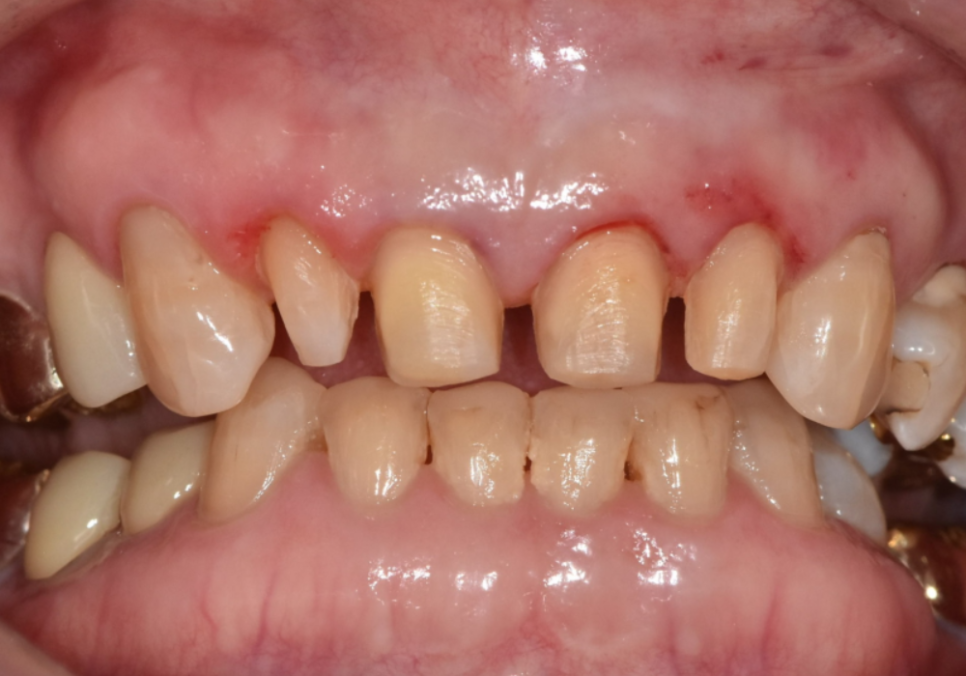

여기에 또 하나의 문제가 있었습니다.

이 분은

윗니가 아랫니를 70~80% 정도 깊게 덮고 있는

과개교합을 가지고 계셨어요.

이렇게 깊게 물리는 고합의 경우,

아래 앞니 끝이 윗니 뒤쪽과 레진에

반복적으로 부딪힐 수밖에 없어요.

250304

그러니 레진을 다시 메워도

조금 시간이 지나면

또 깨지고 떨어질 수밖에 없었던 거였죠.